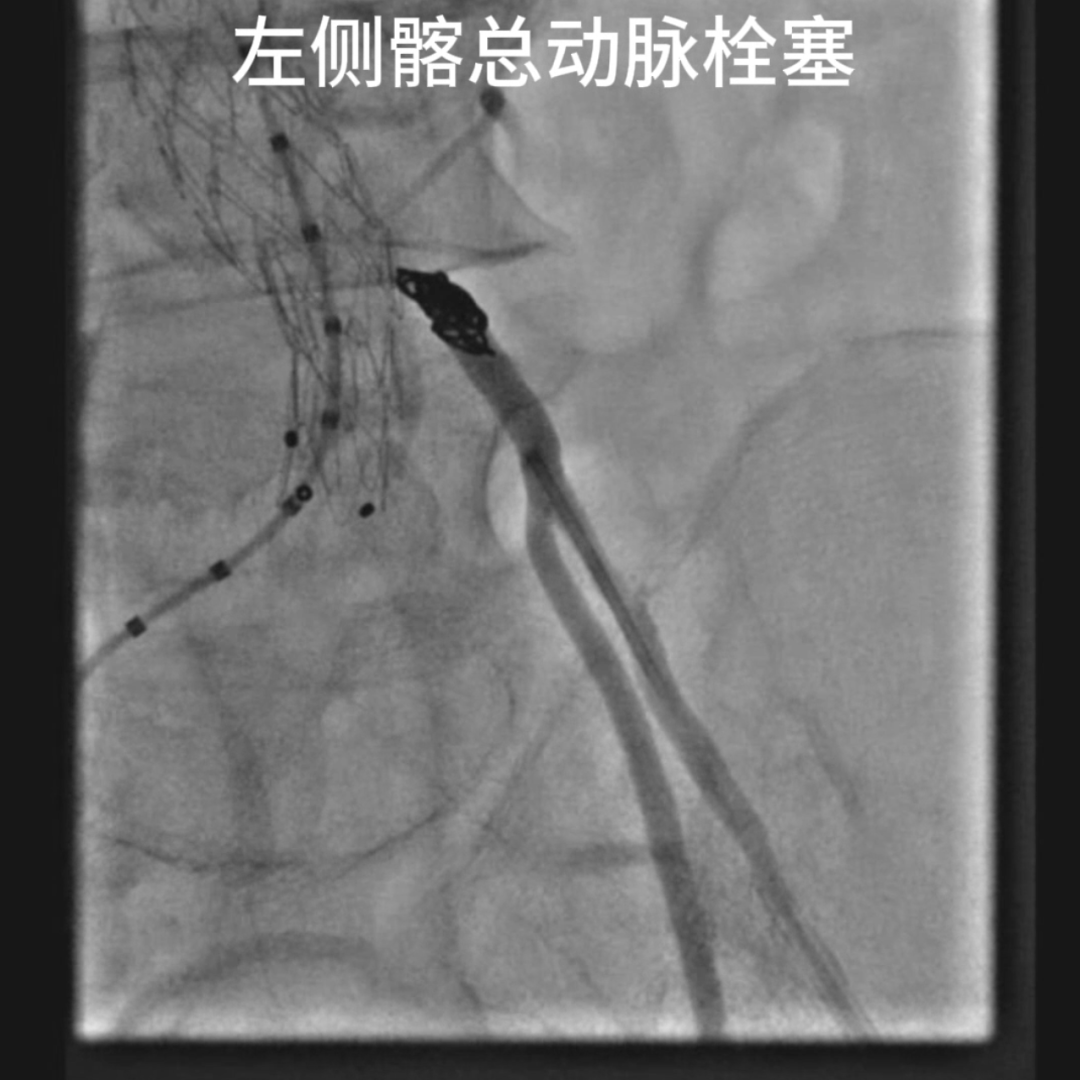

先栓塞肠系膜下动脉,减少潜在Ⅱ型内漏风险。经左侧股总动脉以6-20mm弹簧圈栓塞左髂总动脉根部,彻底封闭左侧髂动脉血流,避免内漏及侧支供血。